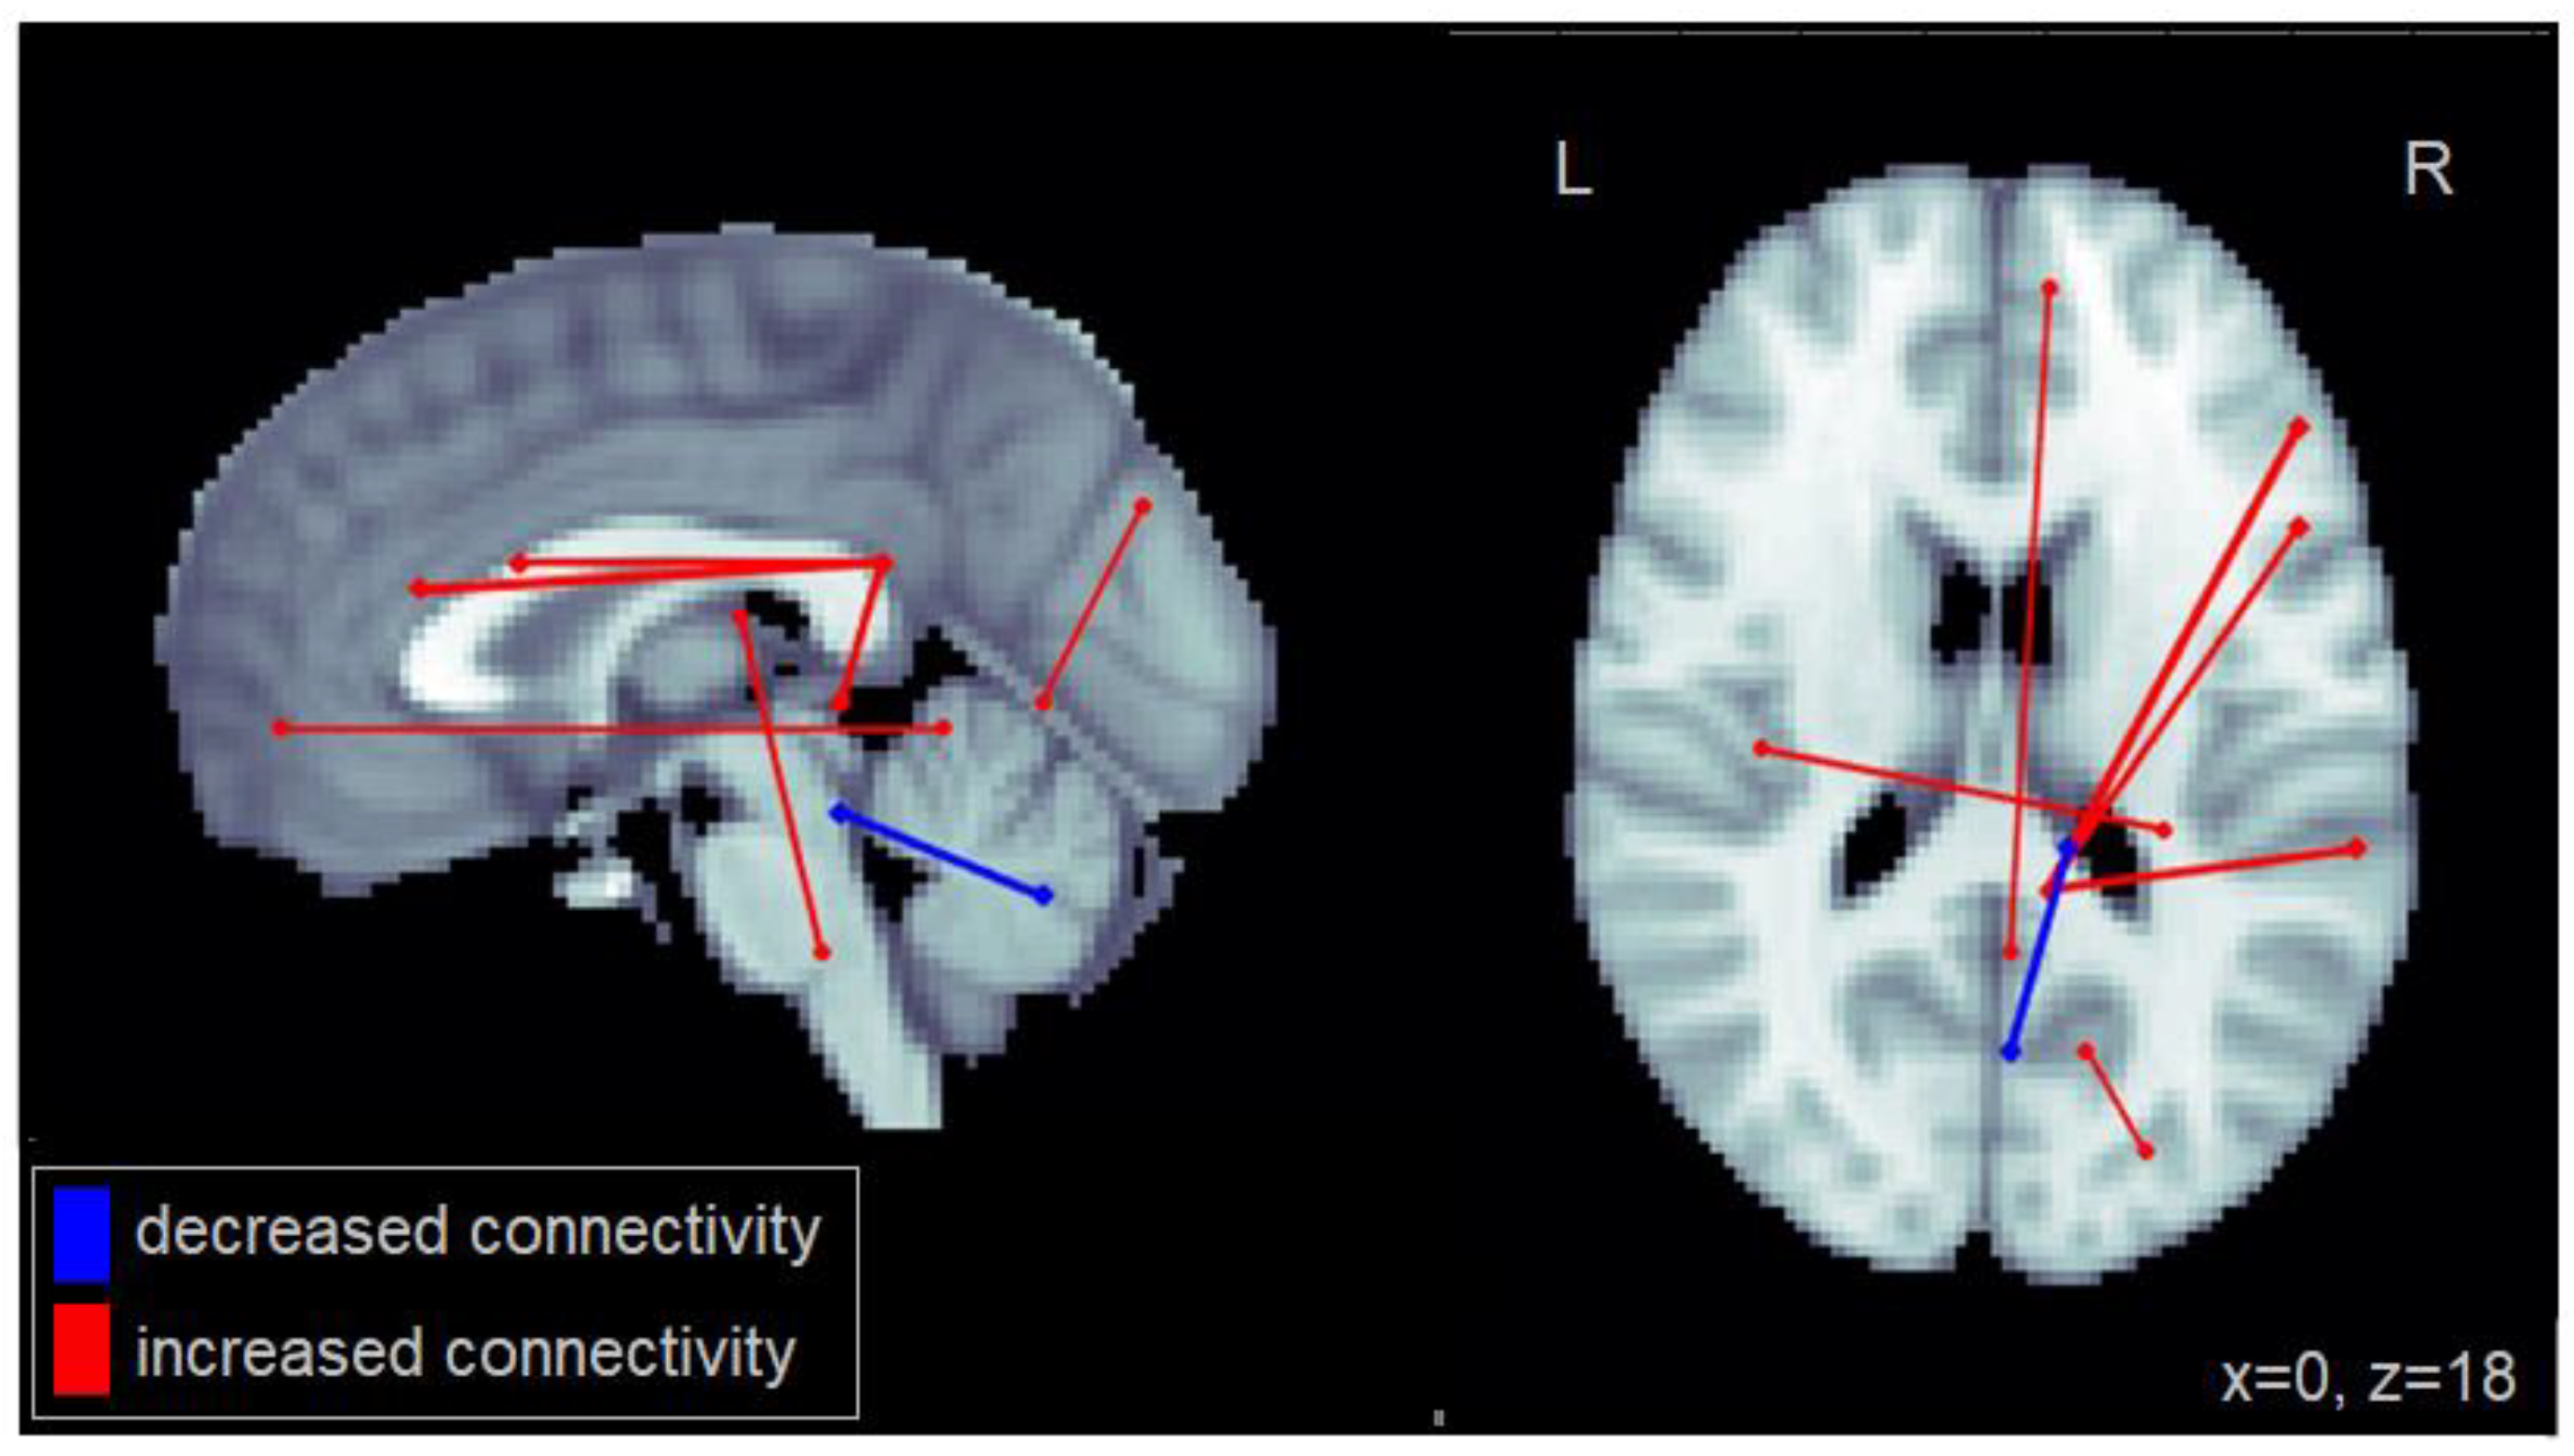

An increased number of lane deviations (centerline crossings + road edge excursions) among patients with MCI was associated primarily with increased connectivity between the right posterior cingulate cortex (PCC), a region of the default mode network (DMN), and regions within the right inferior frontal gyrus as well as the right middle frontal cortex (Figure 2). Furthermore, increased lane deviations were associated with reduced connectivity between cerebellar regions. The complete set of regions showing alterations in connectivity among patients with MCI related to increased lane deviations is reported in Table A2.

Figure 2.

Altered functional connectivity associated with number of lane deviations observed among patients with MCI. Blue lines denote functional connections with reduced connectivity associated with greater lane deviations, red lines denote increased connectivity (significant at FDR = 0.05). Connections are shown as projections in the sagittal and axial plane, with MNI anatomical underlays (slices at x = 0 and z = 18 respectively).